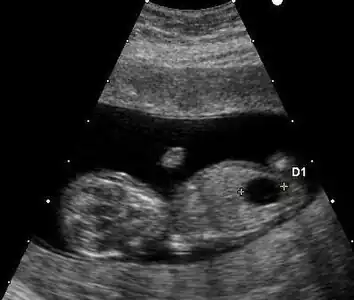

Ultrasound

Prenatal ultrasound can be used to screen for Down syndrome. Findings that indicate increased chances when seen at 14 to 24 weeks of gestation include a small or no nasal bone, large ventricles, nuchal fold thickness, and an abnormal right subclavian artery, among others.[102] The presence or absence of many markers is more accurate.[102] Increased fetal nuchal translucency (NT) indicates an increased possibility of Down syndrome picking up 75–80% of cases and being falsely positive in 6%.[103]